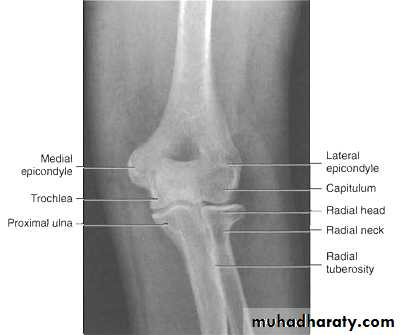

Radiological assessment